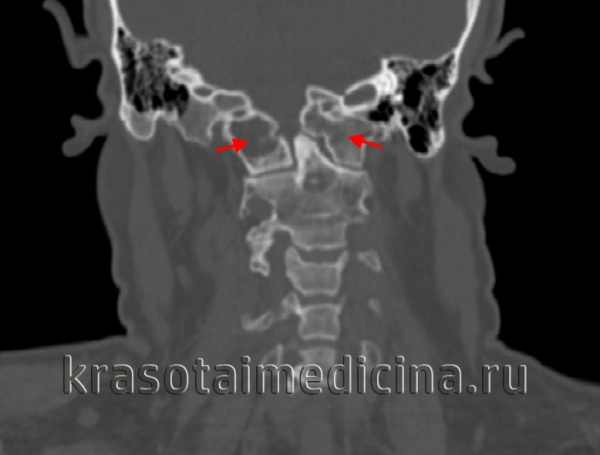

(Слева) КТ, фронтальный срез: расширение суставных щелей атланто-затылочных суставов (АЗС). Небольшие костные фрагменты представляют собой отрывные переломы нижне-медиального края мыщелков затылочной кости. Переломы в области прикрепления связок эквиваленты разрыву этих связок и только усиливают выраженность нестабильности КВС.

(Справа) Т2-ВИ, фронтальная проекция: расширение и гиперинтенсивность сигнала обоих АЗС. Также здесь видно нарушение непрерывности обеих крыловидных связок.